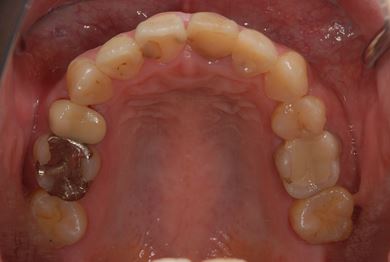

治療後

• 治療後